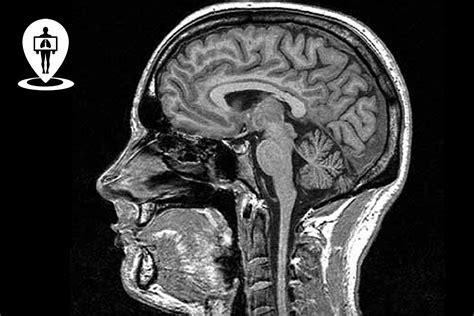

La ricerca neuroradiologica si avvale di tecnologie all'avanguardia, tra cui due magneti ad alto campo (3T) con software avanzato, una TC di ultima generazione e una sala angiografica dedicata. Le immagini vengono elaborate con software di analisi che permettono di estrarre informazioni quantitative su volumetria cerebrale (voxel-based morphometry, surface-based morphometry, ROI-based morphometry), attività cerebrale (task-based fMRI, resting-state fMRI), ultrastruttura della sostanza bianca (trattografia cerebrale) e perfusione. Queste informazioni vengono utilizzate per creare mappe e modelli statistici.

La produzione scientifica in neuroradiologia avviene in stretta collaborazione con altre discipline, principalmente nell'ambito delle neuroscienze cliniche e sperimentali. Risultati significativi sono stati ottenuti negli studi sulla sclerosi multipla, contribuendo all'istituzione del registro nazionale delle neuroimmagini della sclerosi multipla (INNI). Nell'area dei disturbi del movimento, le tecniche avanzate di analisi delle immagini hanno migliorato la comprensione della connettività cerebrale in pazienti con sindrome parkinsoniana, distonia e tremore essenziale.

Le metodologie di imaging avanzato sono state applicate anche per studiare la fisiopatologia del dolore in modelli sperimentali, emicrania, nevralgia trigeminale e fibromialgia. Altre aree di applicazione includono patologie psichiatriche (schizofrenia, psicopatia), malattie neuromuscolari, demenze, tumori (adenomi ipofisari), malattie rare e malattie cerebrovascolari.